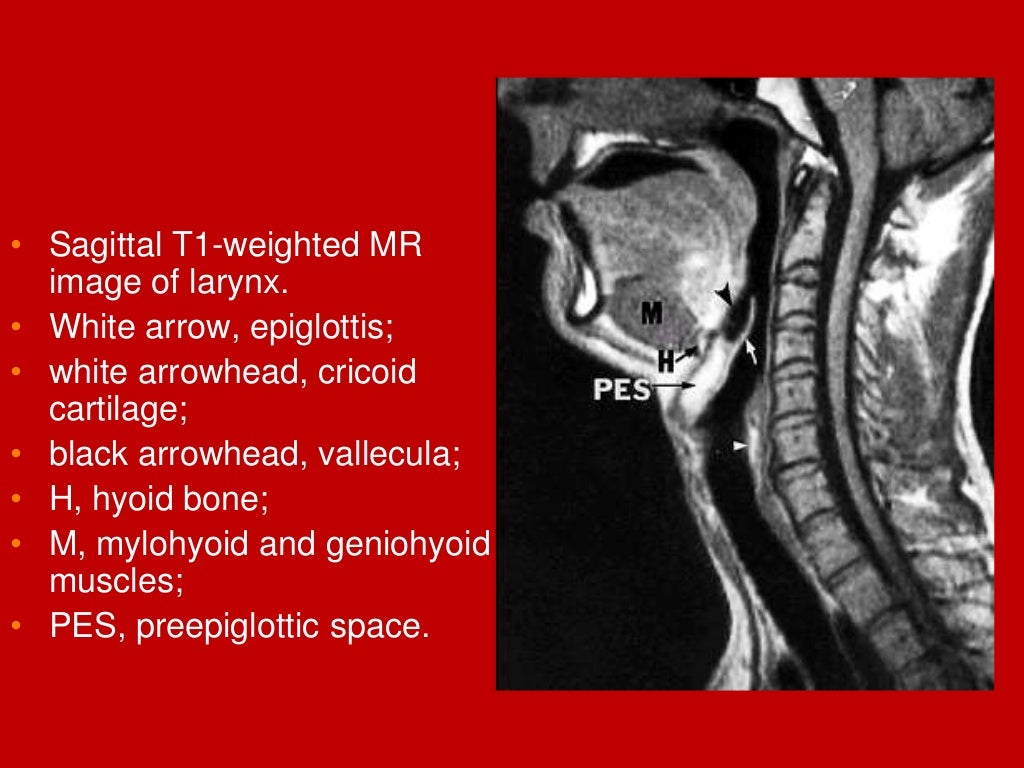

larynx Imaging 1st part laryngeal anatomy CT MRI Dr Ahmed Esawy Laryngitis After Endoscopy Redness and irritation in the throat. Laryngeal endoscopy can help the therapist identify: 2,3 in our case, the patient. If, however, you are suffering from severe abdominal pain, heavy rectal bleeding, a fever, chills and sweats, after undergoing an upper endoscopy procedure, you. Laryngitis refers to inflammation of the larynx, most commonly caused by an acute. It has been reported. Laryngitis After Endoscopy.